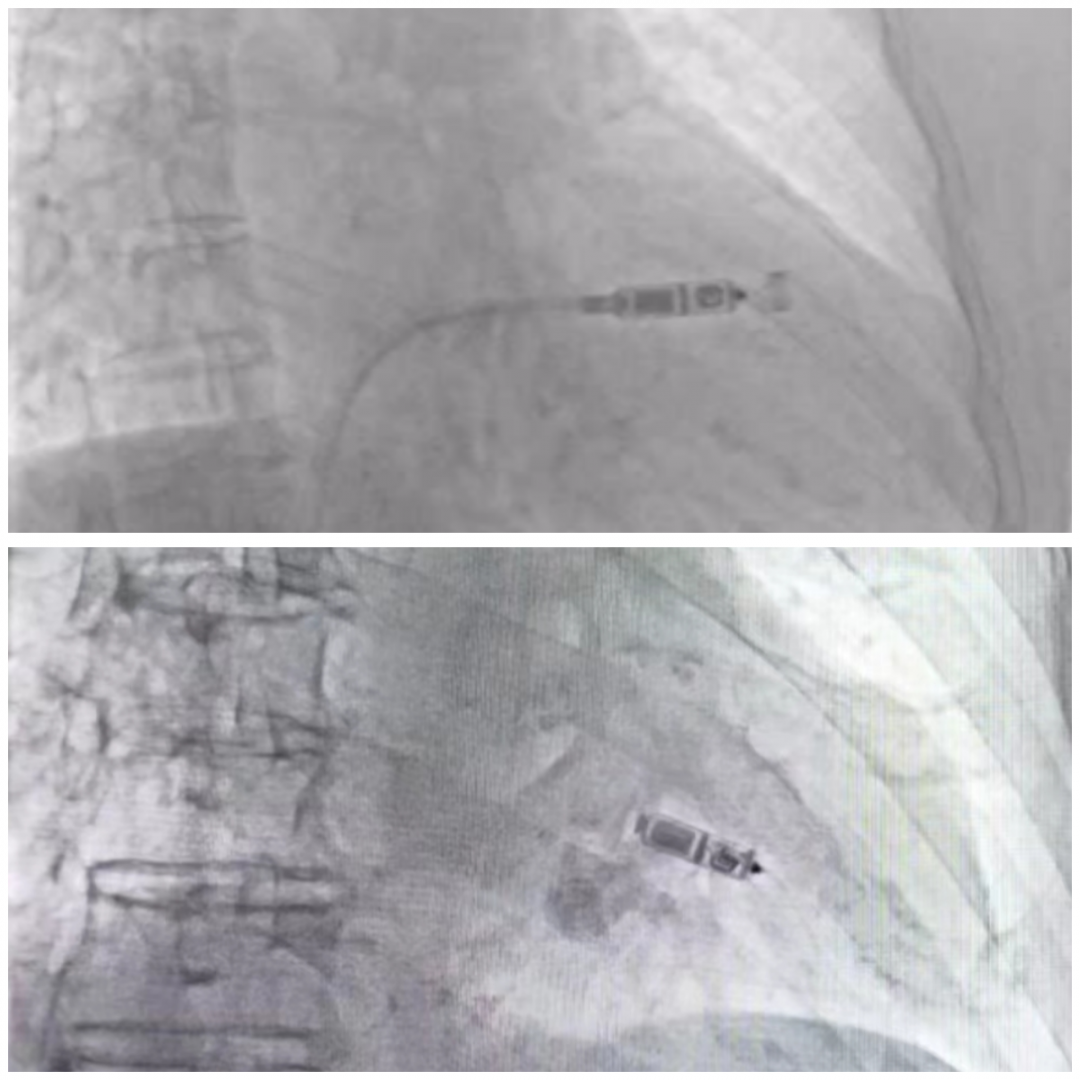

Micra无导线起搏器是一项国际领先的起搏技术,为患者提供了更加准确、安全、高效、舒适的治疗方式。这项技术于2015年2月在阜外医院首次开展,2018年获得了我国CFDA的准入,于2022年12月进入了内蒙古自治区医保目录。只有那些具备无导线起搏全球独立术者认证资质的医生才能独立进行这项工作。

无导线起搏器的植入顺利度和安全性与医生的操作规范和经验直接相关。因此,医生除了需要具备成熟的介入诊疗技术,特别是经验丰富的CIED植入技术外,还需要通过中华医学会心电生理和起搏分会以及中国医师协会心律学专业委员会组织的正规培训。只有在获得培训证书并在资质认证专家的指导下完成一定数量的手术后,才能获得无导线起搏全球独立术者认证资质。

目前临床使用的无导线起搏器Micra 又称“胶囊起搏器”,是当今全球体重最轻、体积最小的起搏器,仅重2克,胶囊大小的脉冲发生器却整合了当今世界最先进的起搏技术元件。